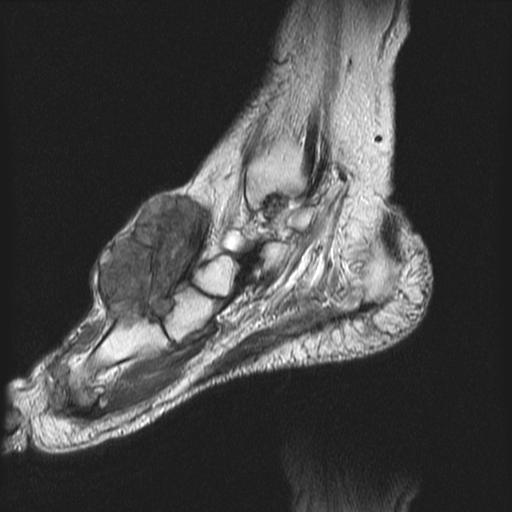

сагиттальная Т2

На серии МР-томограмм получены изображения правого голеностопного сустава.

На тыльной поверхности правой стопы, непосредственно под кожей в области таранной, ладьевидной, клиновидных и оснований от первой до третьей плюсневых костей определяется патологическое образование (тофусы), с распространением на медиальную поверхность стопы, образование неоднородной структуры и МР-сигнала, умеренно гиперинтенсивное на Т1 ВИ, гипоинтенсивное на Т2 ВИ и неоднородного на FAT SAT ИП. Размеры образования 35 х 65 х 40 мм. На постконтрастных изображениях отмечается значительное диффузное усилением интенсивности МР-сигнала от образования. Аналогичные по МР-характеристикам образования, меньших размеров выявляются в левой стопе.

Со стороны костной системы определяются: единичные костно-хрящевые дефекты со склерозом по периферии, диаметром до 3 мм, располагающиеся в субхондральных отделах в области суставных концов большеберцовой и малоберцовой костей, в области прикрепления длинной подошвенной связки к подошвенной поверхности пяточной кости. Множественные дефекты диаметром до 9 мм расположены в области смежных поверхностей ладьевидной и клиновидных костей, некоторые кистовидные дефекты вскрылись в мягкие ткани.

В пяточной кости правой стопы, определяется округлая зона повышенной интенсиновсти МР-сигнала на всех импульсных последовательностях в области блока малоберцовой кости, размерами 7 х 8 мм.

Суставные поверхности уплощены, суставные щели резко сужены, местами определяются краевые костные разрастания.